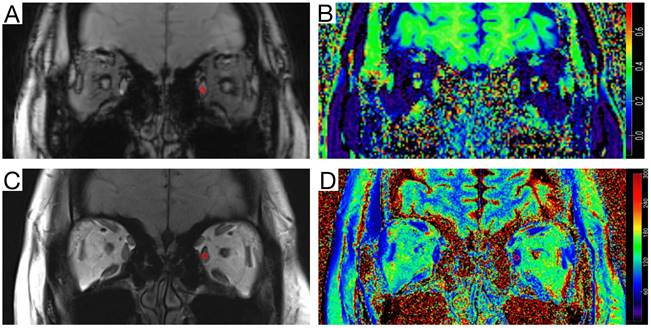

The magnetization transfer ratio (MTR) images were generated using Matlab code (R2021a, Mathworks, MA, USA). The T2-mapping values were carried out using syngo.via (VB20A_HF91) at Siemens workstation (Siemens Healthineers, Erlangen, Germany). MTR was calculated as MTR = 1 - (MT1/MT0) [12, 17], where MT0 is the local signal intensity of the gradient echo sequence without the magnetization transfer saturation pulse, and MT1 is the local signal intensity of the gradient echo sequence with the magnetization transfer saturation pulse. On the MT-off images and T2 anatomical mapping images, a roughly circular region of interest (ROI) was manually drawn on the largest coronal section of the superior, medial, inferior, and lateral rectus muscles. Then the ROI were copy to the MTR image and T2-mapping image (Figure 1). The MTR and T2-mapping values for the left and right eyes were measured and recorded separately. Finally, the mean of MTR and T2-mapping values of the bilateral four rectus muscles (total eight rectus muscles) were used for statistical analysis. The quantitative parameters were measured by two neuroradiologists with more than seven years of experience in head and neck imaging diagnosis, who were blinded to the clinical data. The second radiologist reperformed the measurements after 1 month to assess inter-observer and intra-observer consistency. The first measurement by the second radiologist was used for the final statistical analysis.

Figure 1

Measurement diagram of the magnetization transfer ratio (MTR) and the T2-mapping value. A circular region of interest (ROI) (area of 5-10 mm2) was delineated on the coronal orbital T2 anatomical mapping image with the largest cross-sectional area of the ocular muscles of myasthenia gravis (MG) patients and healthy volunteers. The ROI was then copied to the T2-mapping image, and the corresponding T2 signal values were recorded. On the same level of the Magnetization transfer off (MT-off) map, the same ROI (area of 5-10 mm2) was delineated, the ROI was copied to the MTR image, and the corresponding MTR value was recorded. A, MT-off image. B, MTR image. C, T2-anatomical mapping image. D, T2-mapping image.